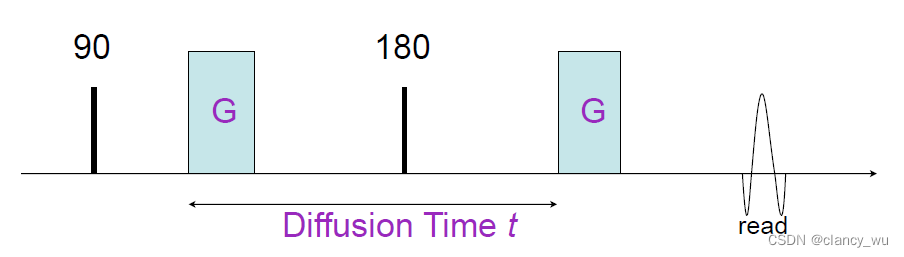

所以其实纤维束构建的本质就是通过数学方法来计算Diffusion。说到计算,核磁里有一个技术,Pulsed-Gradient Spin-Echo Sequence(脉冲梯度自旋回波序列),就是在时间t内施加一个x方向的强磁场梯度,观察分子在前后运动的距离,就可以得出来弥散速度。

其实在临床上,我们看病人的核磁图象时,也能看到患者非弥散加权像-弥散加权像-两者比值这三张图,图的意义就是来自于上述思想。

因此,弥散速度的对比,我们可以通过两个变量来建模估算,一个是场强大小和场强方向。

场强大小,其实就是我们研究DTI像经常会看到的变量,即B值,B0,B1000,B3000等。